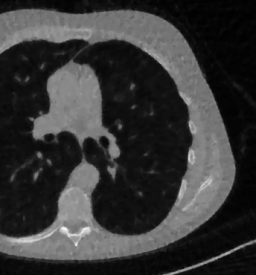

Here we present the results of RISING applied to the Mayo data set introduced in paragraph 4.1. As previously mentioned, we consider two sparse-view CT geometries, namely P360,360subscript𝑃360360P_{360,360} and P360,180subscript𝑃360180P_{360,180}. In Figure 4 we report the results for the P360,360subscript𝑃360360P_{360,360} protocol, achieved on one image of our test set. The top-left image represents the xRIS=x(15)subscript𝑥𝑅𝐼𝑆superscript𝑥15x_{RIS}=x^{(15)} reconstruction. Even if only a small number of iterations are performed, the main structures of the abdomen are visible; however, the image is still blurry. In the xISsubscript𝑥𝐼𝑆x_{IS} image, shown in the upper-right corner, we notice that the TV regularizer has acted to totally eliminate the artifacts and noise, improving the uniformity of the image in the inner structures. When compared to the ground-truth solution in Figure 2, the contours of the details in xISsubscript𝑥𝐼𝑆x_{IS} appear slightly jagged, differently from xGTsubscript𝑥𝐺𝑇x_{GT} where they are neat but, usually, corrupted by artifacts. The bottom row of Figure 4 shows the two xLPPsubscript𝑥𝐿𝑃𝑃x_{LPP} and xINGsubscript𝑥𝐼𝑁𝐺x_{ING} images, respectively from left to right. It is evident that xLPPsubscript𝑥𝐿𝑃𝑃x_{LPP} has retrieved many details but it presents noisy components, reflecting the features of its target image xGTsubscript𝑥𝐺𝑇x_{GT}. Our solution xINGsubscript𝑥𝐼𝑁𝐺x_{ING} is less corrupted, since the low-contrast regions are correctly preserved and the noise is not visible. These observations are confirmed by Figure 5, which plots the intensity profiles taken over the red line in the second crop (Figure 2). In our approach (on the right) the CNN has accurately learnt the f𝑓f map of (8) and the xINGsubscript𝑥𝐼𝑁𝐺x_{ING} red profile mostly overlaps the black one. On the contrary, the xLPPsubscript𝑥𝐿𝑃𝑃x_{LPP} profile (on the left) is more distant from its target reference.

Figure 4: Results on a test image from the Mayo data set, under the P360,360subscript𝑃360360P_{360,360} CT protocol. Top-left: xRISsubscript𝑥𝑅𝐼𝑆x_{RIS}; top-right: xISsubscript𝑥𝐼𝑆x_{IS}; bottom-left: xLPPsubscript𝑥𝐿𝑃𝑃x_{LPP}; bottom-right: xINGsubscript𝑥𝐼𝑁𝐺x_{ING}.